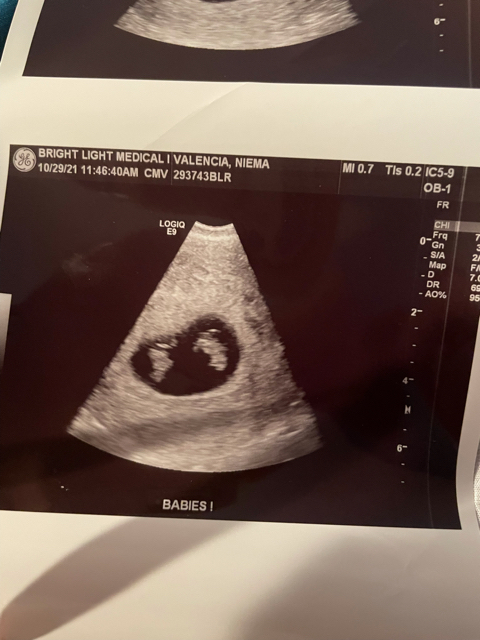

Hi ladies! Expecting TWINS! Unknown Duedate.

I had a miscarriage at 6 weeks on Sep. 5th. Got a positive test and HCG blood test on Oct. 6th. Never got a period. Doctor wanted to make sure it wasn’t leftover HCG from previous pregnancy but it was confirmed that my numbers were at a zero 3 weeks prior to getting a positive. Now, I had a dating ultrasound today and I’m wondering why don’t I see that separation like I’m seeing on other twin ultrasounds. I don’t go to get results for another 2 days. All I know is there are 2 yolk sacs, and 2 babies. They’re just there dangling. I guesstimated about 7 weeks or so. I’m excited!!! But of course nervous about everything.